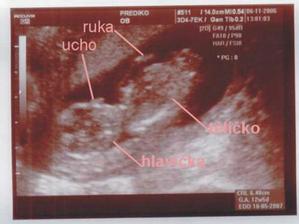

Nedovedete si představit to velké štěstí...které nás potkalo, je to prostě náš ZÁZRAK. Teď jsem sice plná obav a strachu o miminko, i nějaké komplikace se vyskytli, ale snad všechno dobře dopadne, a nám se v květnu, rok po naší svatbě, narodí krásné a zdravé miminko...náš malý - Velký Zázrak.